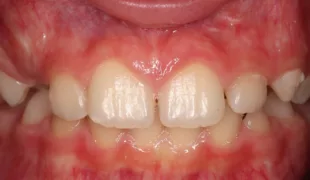

Fall 2: Versorgung einer Initialkaries an Zahn 14 und später an 15

Die 26 Jahre alte Patientin störte sich an der approximalen Lücke zwischen den Zähnen 14 und 15, da sich hier ständig Speisereste impaktierten. Bei der klinischen Inspektion fiel die Initialkaries distal an Zahn 14 auf (Abb. 7). Die Patientin wurde dahingehend beraten, den Spalt mit einer minimalinvasiven Kompositrestauration zu versorgen – bei zeitgleicher Exkavation der Karies an Zahn 14. Nach Exkavation und Präparation des Defektes (der sich als deutlich ausgeprägter präsentierte als anfangs angenommen) erfolgte identisch zu Fall 2 die Ausformung der Kavität mit einer Teilmatrize (Danville ultra thin flex), einem Kunststoffkeilchen (G-Wedge) und der Separation mit einem NiTin-Prämolaren-Spannring (re-invent, Abb. 8).